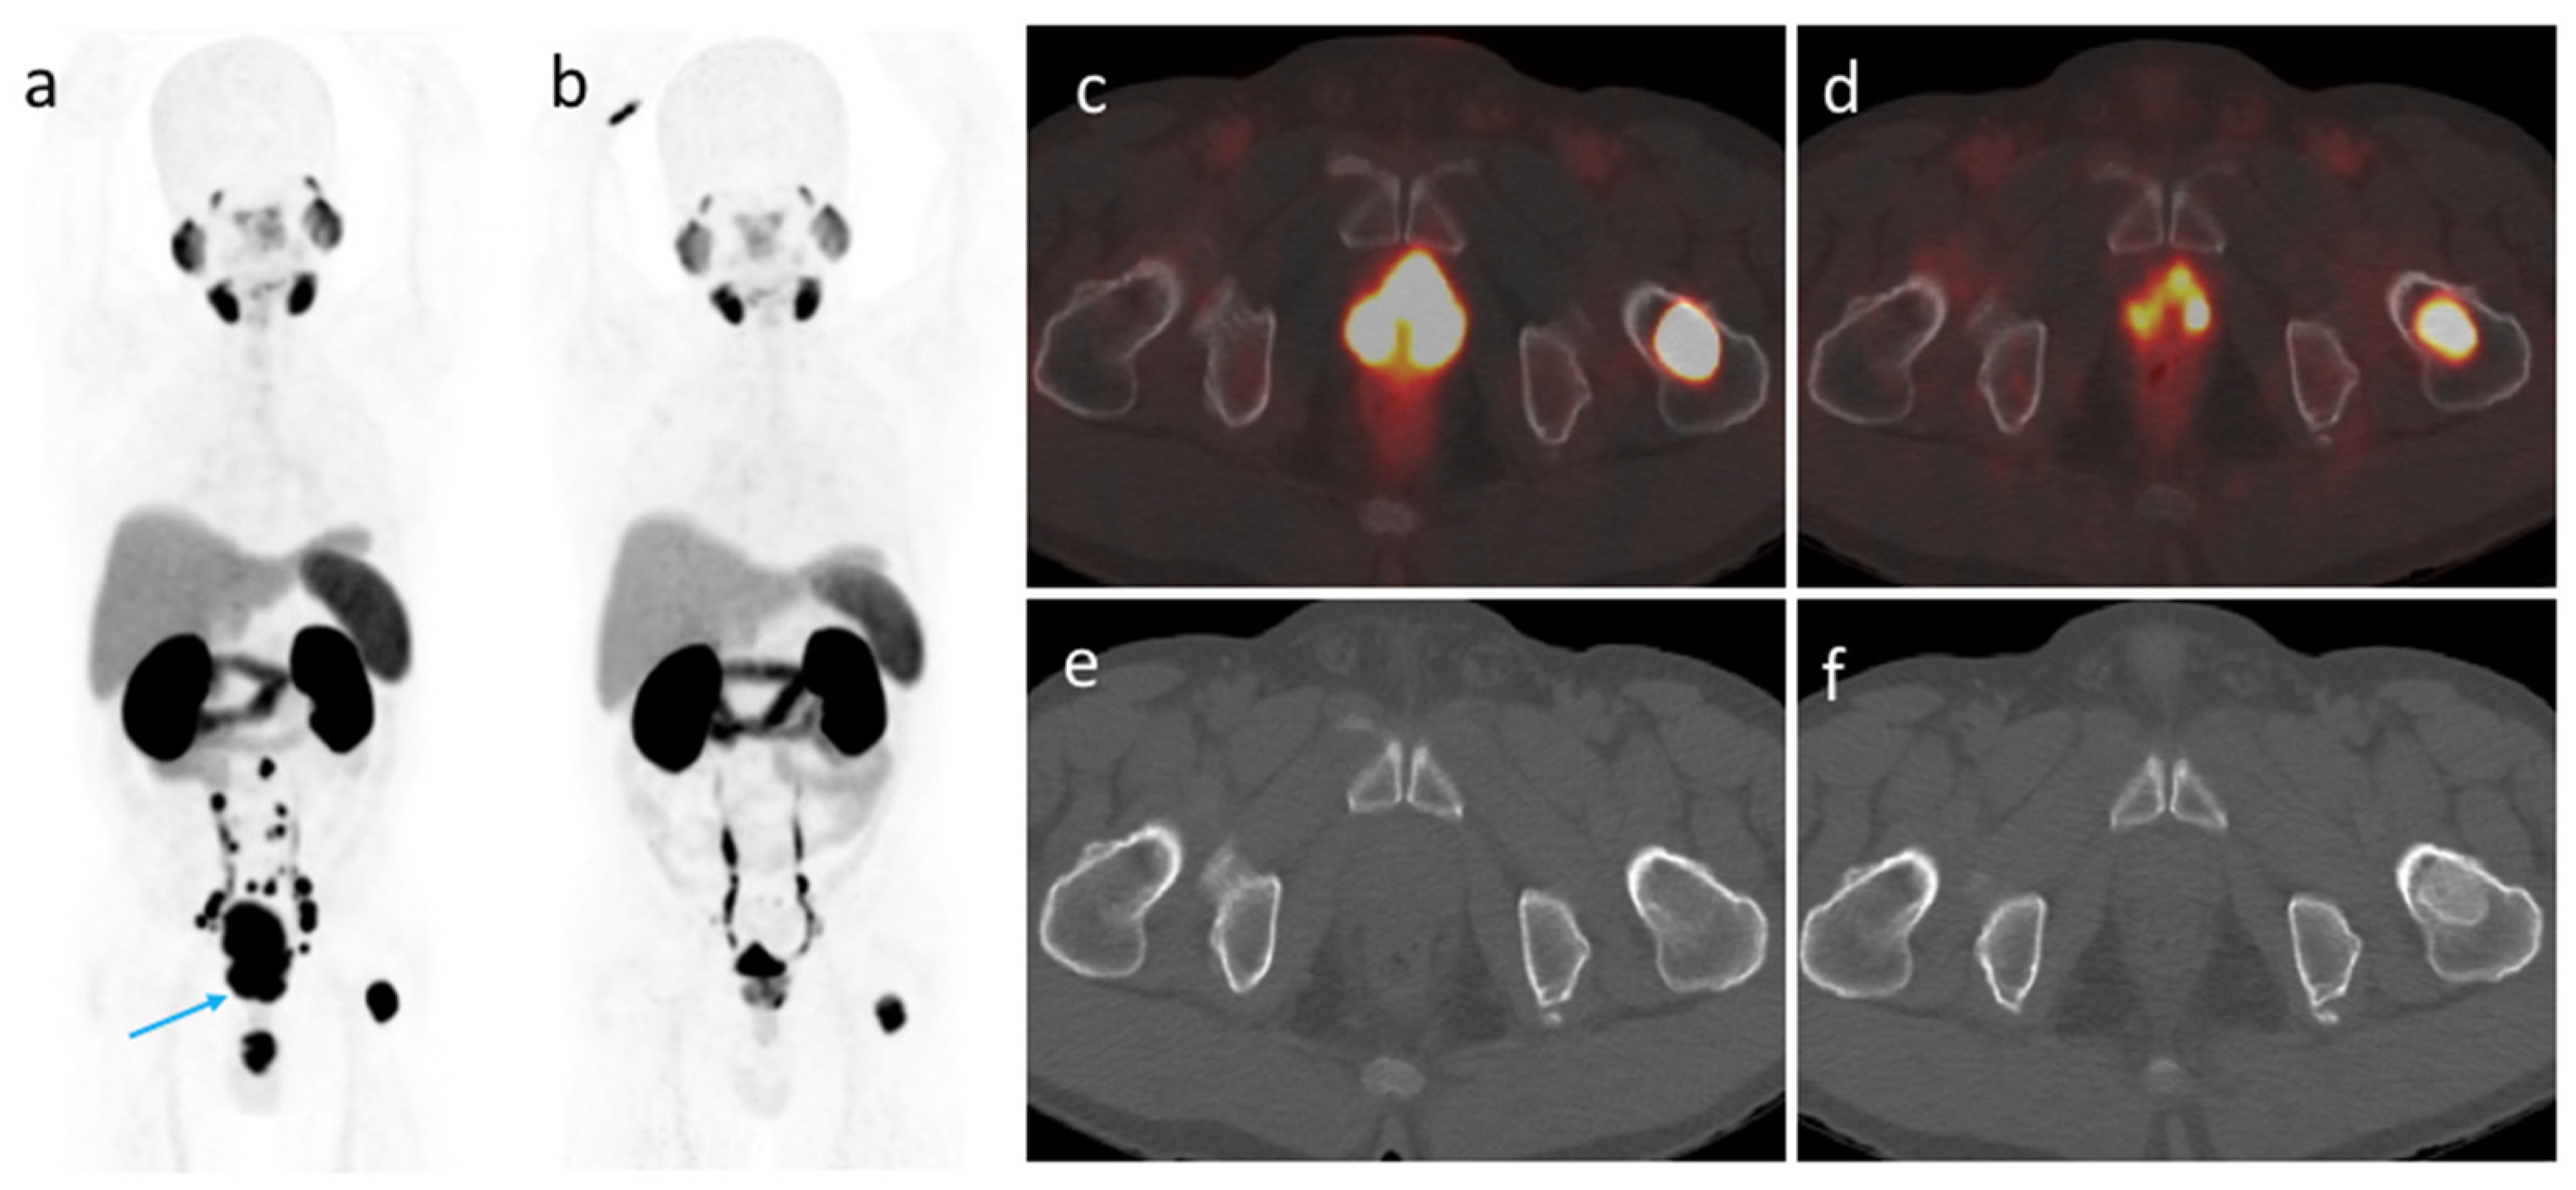

Figure 3.

A 60-year-old patient with metastatic prostate cancer (clinical stage IVB, PSA 11.54 ng/mL, Gleason score 5 + 4). (a) A maximum intensity projection obtained before treatment revealed the prostate tumor (blue arrow) accompanied by urine contamination. (b) A second scan after three months of leuprorelin therapy showed a significant response to treatment. (c) and (d) Axial fused PET/CT images revealed a decreased prostate tumor metabolic volume and a reduced tracer uptake. The SUVmax of a left femoral metastatic lesion decreased from 70.41 to 20.32. (e) and (f) A second morphological imaging examination revealed a bony sclerotic change of the left femoral metastatic lesion, which was unexpected based on PET/CT findings.